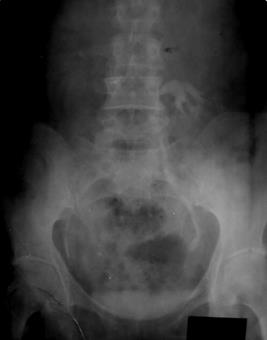

| Рис. 6.5. Прицельная рентгенограмма таза. Цистография. Определяется обширный дефект наполнения связанный со стенкой мочевого пузыря с неровными контурами. Рак мочевого пузыря. |